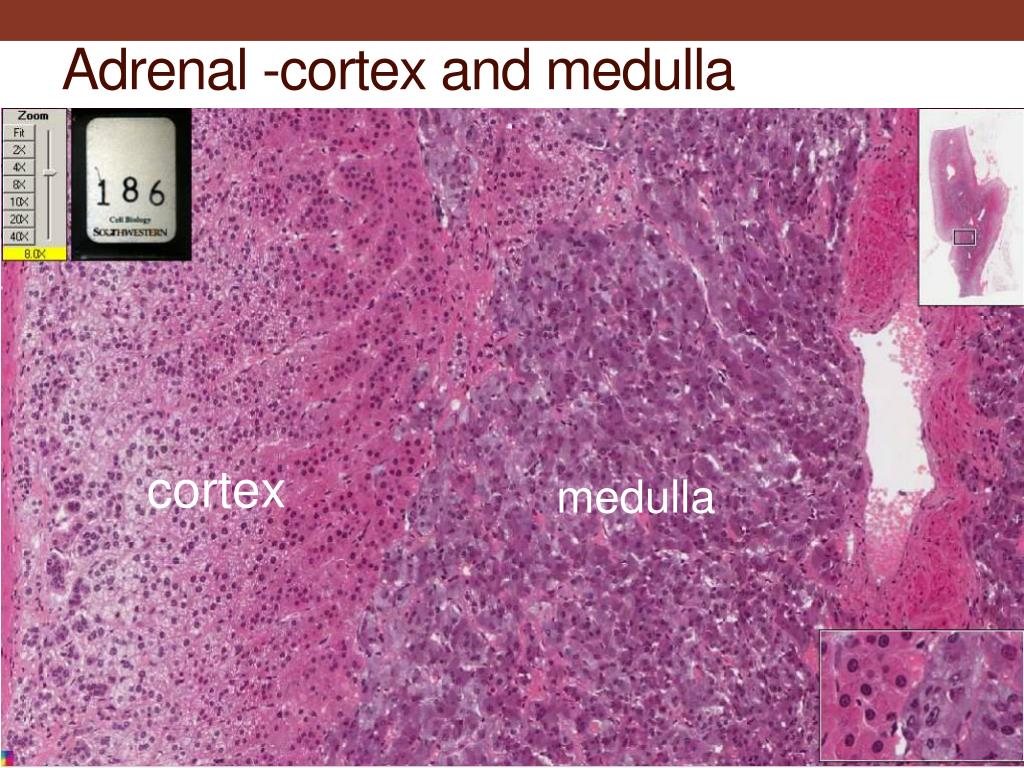

adrenal gland diagram Google Search Biology Diagrams Anatomy . As mentioned, the adrenal glands are two small, roughly triangular glands that sit directly on top of the kidneys. The two major parts of the adrenal gland are the cortex and the medulla. The gland is surrounded by an adipose (fatty) capsule, which acts as a protective barrier. These two major sections of the adrenal are called the adrenal medulla (inner layer), and the adrenal cortex (outer layer). The Adrenal Medulla: The adrenal medulla comes from the neural crest (i.e. embryological basis similar to your central and peripheral nervous systems). It contains homogenous sheets of cells organized into nests.

Adrenal medulla. The adrenal medulla is embedded in the centre of the cortex of each adrenal gland. It is small, making up only about 10 percent of the total adrenal weight. The adrenal medulla is composed of chromaffin cells that are named for the granules within the cells that darken after exposure to chromium salts.

The adrenal cortex tends to be fattier and thus has a more yellow hue. The adrenal medulla is more of a reddish-brown color. A thick capsule consisting of connective tissue surrounds the entire adrenal gland. The adrenal cortex is much larger than the smaller medulla, accounting only for approximately 15% of the gland. What is the anatomy of the adrenal cortex? You have two adrenal glands — one on top of each kidney. They contain the cortex, the largest part of the gland, and the medulla, the smaller inner part. Your adrenal gland is highly vascular, with as many as 50 arterial branches providing its blood supply. When does the adrenal cortex develop? Blood first flows through the adrenal cortex and then drains into the adrenal medulla. Adrenal hormones are released into the circulation via the left and right suprarenal veins. Figure 17.6.1 - Adrenal Glands: Both adrenal glands sit atop the kidneys and are composed of an outer cortex and an inner medulla, all surrounded by a connective

Anatomical Structure. The adrenal glands consist of an outer connective tissue capsule, a cortex and a medulla.. Veins and lymphatics leave each gland via the hilum, but arteries and nerves enter the glands at numerous sites.. The outer cortex and inner medulla are the functional portions of the gland. Adrenal Medulla: The hormones secreted by the adrenal medulla are not essential for the survival. Conclusion. Adrenal cortex and adrenal medulla are two major cell layers of the adrenal gland. The adrenal gland is located on the top of the kidney. Both adrenal cortex and adrenal medulla secrete hormones to regulate the functions of the body.